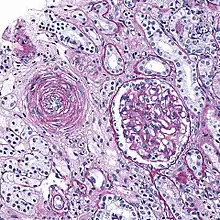

Hyaline arteriolosclerosis

Also arterial hyalinosis and arteriolar hyalinosis refers to thickening of the walls of arterioles by the deposits that appear as homogeneous pink hyaline material in routine staining.[3] It is a type of arteriolosclerosis, which refers to thickening of the arteriolar wall and is part of the aging process.[4]

Hyperplastic arteriolosclerosis

This is a type of arteriolosclerosis involving a narrowed lumen.[4] The term "onion-skin" is sometimes used to describe this form of blood vessel[8] with thickened concentric smooth muscle cell layer and thickened, duplicated basement membrane. In malignant hypertension these hyperplastic changes are often accompanied by fibrinoid necrosis of the arterial intima and media. These changes are most prominent in the kidney and can lead to ischemia and acute kidney failure.